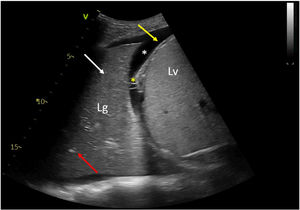

An anteroposterior chest radiography showed an area of lung consolidation in lower right lobe, indicating pneumonia (see Fig. 1). The lung ultrasound showed lobar consolidation, air bronchogram, pleural effusion and fibrin (see Fig. 2), as well as hyperechoic opacities that move centrifugally with respiration (dynamic air bronchogram) (see suppl. material 1). The patient was discharged alive after 2 months.